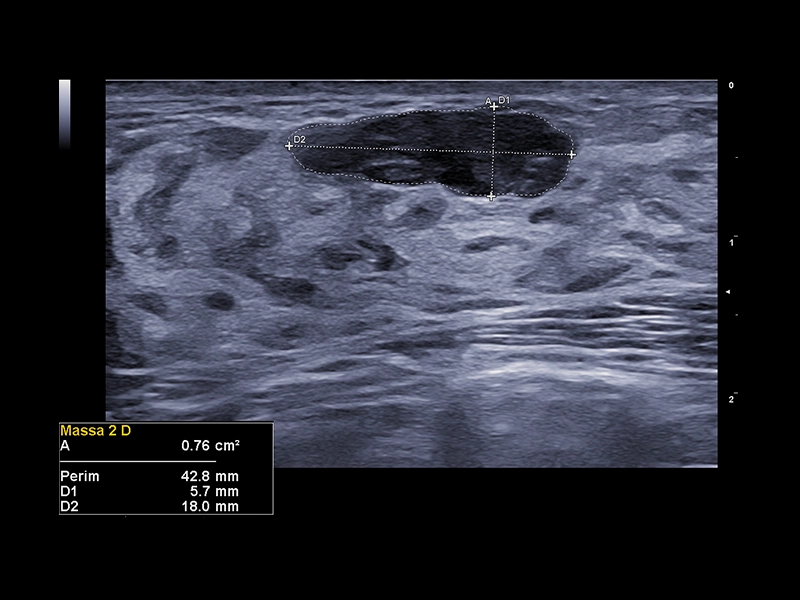

MyLab™X9 - Breast 02

MyLab™X9 - Breast 02